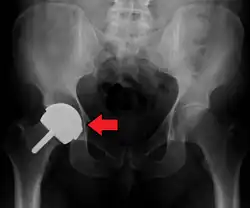

Dislocation

Dislocation (the ball coming out of the socket) is one of the most common complications. Hip prosthesis dislocation mostly occurs in the first three months after insertion, mainly because of incomplete scar formation and relaxed soft tissues.[15] The chance of this is diminished if less tissue is cut, if the cut tissue is repaired and if large diameter head balls are used.[17] Surgeons who perform more operations tend to have fewer dislocations. Important factors which are related to dislocation are: component positioning, preservation of the gluteal muscles and restoration of leg length and femoral offset.[18] Keeping the leg out of certain positions during the first few months after surgery further reduces risk.

Dislocations occurring between three months and five years after insertion usually occur due to malposition of the components, or dysfunction of nearby muscles.[15] Risk factors of late dislocation (after five years) mainly include:[15]